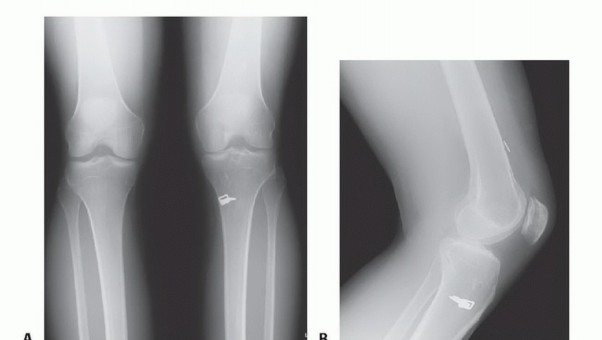

DEFINITION Patellofemoral pain is a common symptom in active adolescents and adults. The diagnosis of patello…